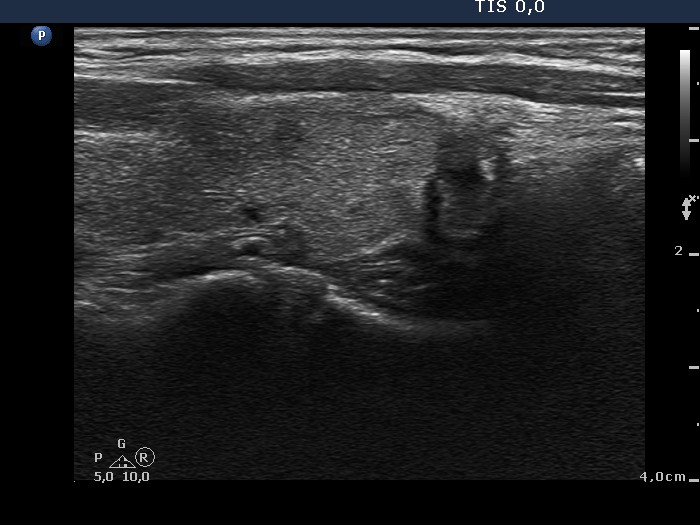

100 consecutive cases of papillary cancer - case 032 (ultrasonographic picture 8)

Lower third of the left lobe, longitudinal scan.